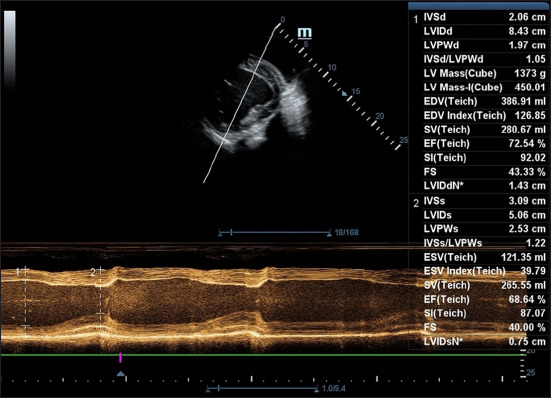

Materials and methods: Six healthy adult mules (18.83 ± 0.75 years; 263.83 ± 39.34 kg) were evaluated using standard two-dimensional and M-mode transthoracic echocardiography. Measurements were obtained before sedation (standing) and 13-min post-anesthetic induction (dorsal recumbency). Each mule received an intravenous injection of acepromazine (0.04 mg/kg), xylazine (1.6 mg/kg), diazepam (0.1 mg/kg), and ketamine (2.2 mg/kg). Key echocardiographic parameters included interventricular septum thickness (interventricular septum in diastole and interventricular septum in systole), left ventricular internal diameters (left ventricular internal diameter in diastole and left ventricular internal diameter in systole [LVIDs]), posterior wall thickness (left ventricular posterior wall in diastole and left ventricular posterior wall in systole), ejection fraction (EF), and fractional shortening (FS). Statistical comparisons were made using paired t-tests and Wilcoxon signed-rank tests (p < 0.05).

Results: Heart rate, EF, and FS significantly decreased post-anesthesia (p < 0.01), indicating reduced systolic function. Specifically, LVIDs increased from 4.60 ± 0.65 cm to 6.26 ± 0.48 cm (p < 0.01), while no significant changes were observed in diastolic parameters or respiratory rate. Anesthetic induction was smooth and graded as good to excellent in all cases.